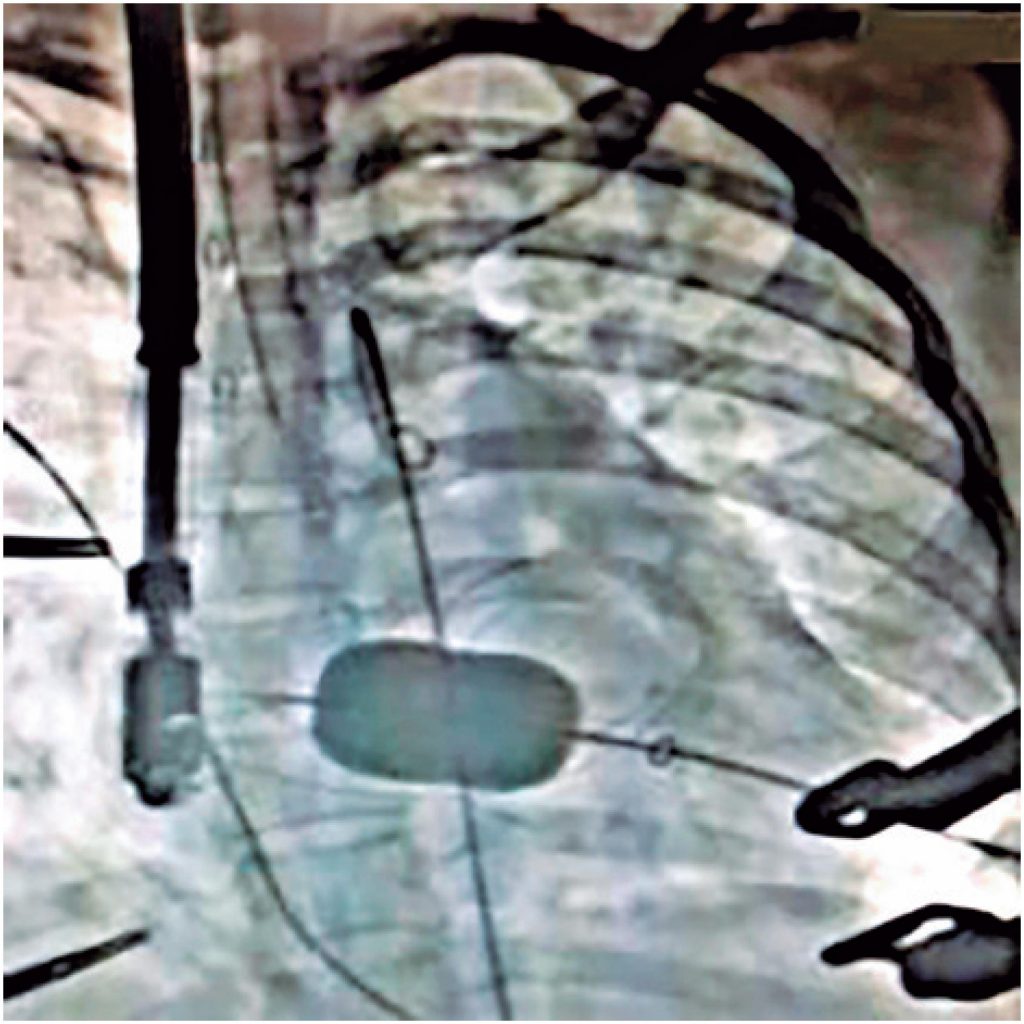

This report describes a therapeutic alternative for correction of severe mitral stenosis causing high-response atrial fibrillation, and consequent syncope in a woman at 8 weeks gestational age. A percutaneous valvuloplasty attempt failed, because the transseptal puncture was not possible, and a definitive resolution was achieved by transapical valvuloplasty, via left thoracotomy through an inframammary incision, with direct access to the mitral valve. Since this was an original and complex procedure, this case is of relevant importance in the treatment of severe mitral stenosis in patients whose conditions render a conventional procedure impossible.